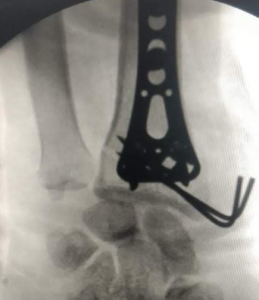

PROFILE TRAINING AND PRESENTATION Dr. Niranjanan Recieving Diploma SICOT degree in Rome, Italy Dr. Niranjanan being awarded fellowship certificate at Indian spinal injuries centre CLIINIC SOME OF Dr. NIRANJANAN's CASES